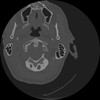

7 HUESO,,Vol,0.5,HUESO,,